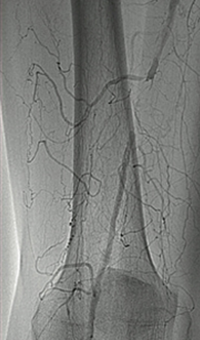

Case CLI with right foot ulcer thrombectomy: Posterior and anterior tibial

Case CLI with Right Foot Ulcer Thrombectomy pre-procedure arteriogram.

Arteriogram of posterior and anterior tibial post-CDT

PT and AT remained occluded following overnight CDT infusion of lytic

Case CLI with Right Foot Ulcer Thrombectomy post-AngioJet Solent Dista.

Post-AngioJet™ Solent™ Dista thrombectomy with PowerPulse™ delivery

AngioJet Solent Dista Catheter used in Power Pulse mode in both AT and PT. 30 min dwell in  AT and 45 min dwell in PT. Followed by Solent Dista Catheter used in thrombectomy mode

Case CLI with Right Foot Ulcer Thrombectomy post-procedure arteriogram.

Post-procedure arteriogram

Image following ballooning of small focal lesion in PT